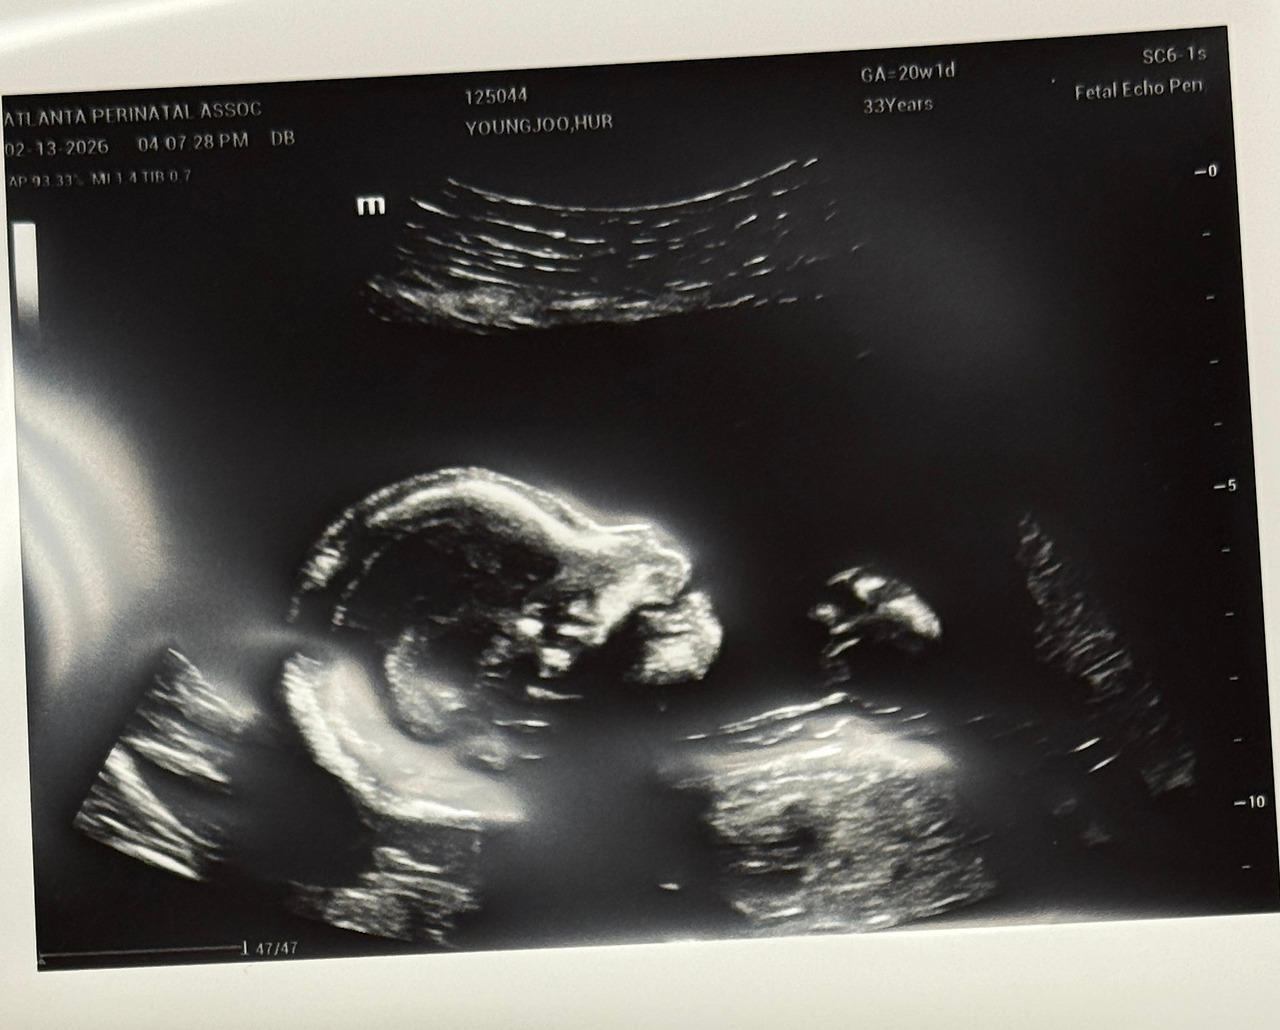

20주 정밀 초음파에서 본 나무. 꼬물꼬물 움직이는게 신기했다.